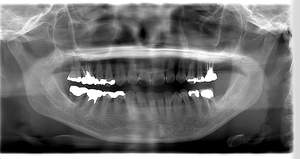

インプラント治療の症例4

レントゲン写真

- Befor

- After

| 年齢 | 50代・男性 |

|---|---|

| 主訴 | 部位:左下6番7番 主訴:左下奥歯腫れて痛い。 |

| 治療内容 | 左下6番抜歯、左下6番7番骨造成、インプラント埋入 |

| 治療費 | 合計:1,232,000円 ・内訳 診断料:55,000円 サージカルガイド2本:66,000円 GBR:110,000円×2本 埋入料:165,000円×2本 静脈内鎮静麻酔:77,000円 2次OPE:22,000円×2本 仮歯:55,000円×2本 上部構造(フルジルコニア):165,000円×2本 (2023年1月現在) |

| 治療期間 | 約8ヶ月 |

| リスク・副作用 | リスク・副作用 |

| 治療方針 | 元々支台歯に負荷がかかりやすいとされている延長ブリッジを抜歯し、1本単体でしっかりかめるようにインプラントを2本埋入した。骨吸収も進んでいたため、※GBR法で骨造成を同時に行った。 治療と並行して、全顎的な歯周病治療も行い、今後は歯周病が進行しないよう、こまめにメンテナンスに通っていただく。 |

| 特記事項 | ※1 GBR・・・骨再生誘導法。骨の高さや厚みを人工骨や人工膜などを使用し再生する方法 |

| 担当者所見 | 6番は歯根分割された被せ物が7番の欠損部との延長ブリッジとされており、強い咬合と歯周病も相まって負荷がかかり動揺し、歯として機能しなくなったため、抜歯となった。 |